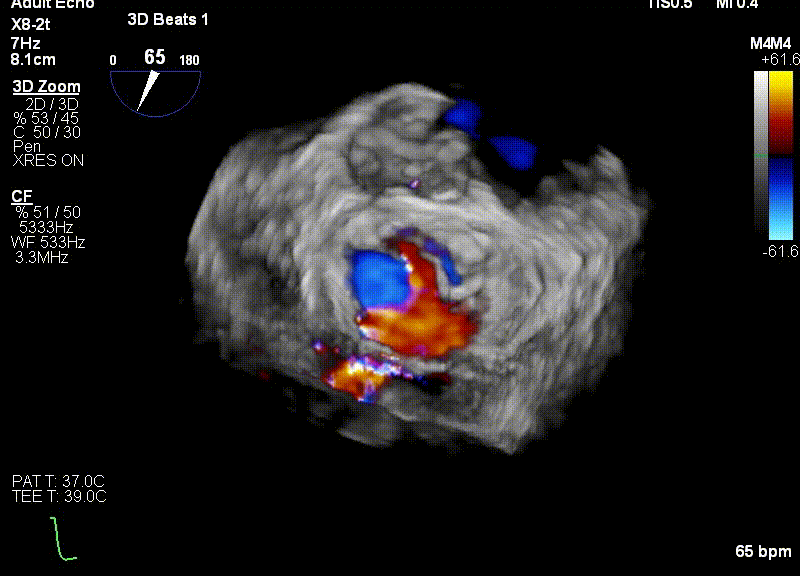

经食道超声引导后,王建安教授将二尖瓣夹NTR夹取C1区瓣叶,准确成功捕获C1前叶和后叶反流最严重区域,并予夹合。使二尖瓣在收缩期由大的单孔变成一大一小的双孔,显著减少了二尖瓣反流。

反复测试二尖瓣夹的稳定性,食道超声复查提示二尖瓣夹C1区反流有效改善,术后反流量由术前的4+变为术后的<1,遂精准释放二尖瓣夹。